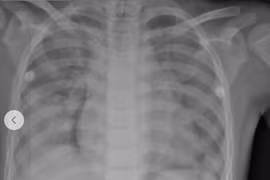

Bệnh nhi được chẩn đoán ngạt nước, phù phổi cấp, thiếu oxy não và viêm phổi hít nguy kịch đã được cứu sống sau 3 tuần hồi sức tích cực.